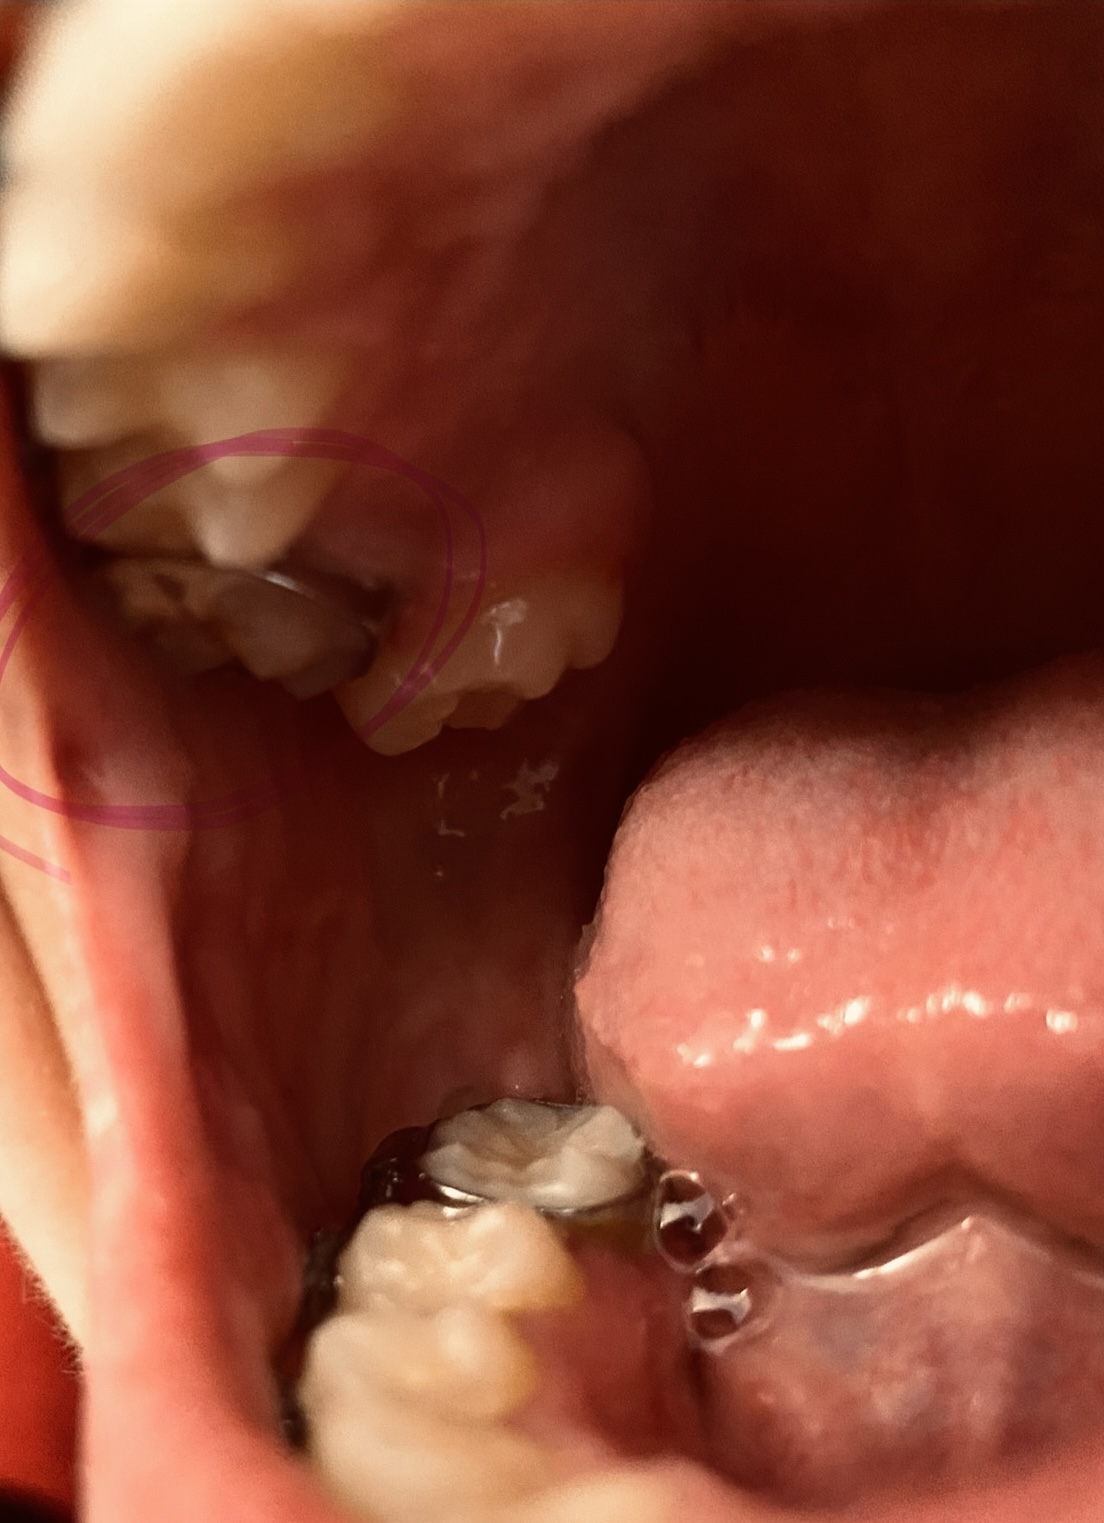

My daughter has some spacing in her teeth. Some misshaped teeth and her top and bottom row doesn’t match up and I wanted to know from the looks does it look like she needs braces? She also bites down on her jaw alot

Its hard to diagnose from the picture alone, with her mouth open and not in centric (closed and relaxed) occlusion. It appears from the picture that she has most or all of her permanent dentition. This is the perfect time to schedule a complimentary consultation with a preferred orthodontist in your area. Its not clear what you mean by "biting down on her jaw a lot", however I am assuming it means her bite is different than yours and its possible that it feels uncomfortable to her. Spacing and small or misshaped teeth are cosmetic, however if she is in malocclusion, these can all be addressed with orthodontics. Most orthodontists will evaluate your daughter at little to no cost to you. It is always a good idea to get more than one opinion prior to making a decision with treatment.